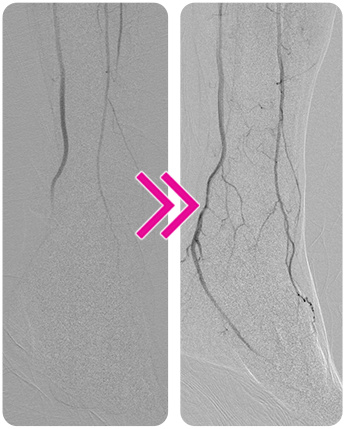

Removal of Below-the-Knee Thrombus with the Pounce™ LP Thrombectomy System

Charles DeCarlo, MD

A man in his mid 60s presented to the emergency department with severe pain in his right foot. Patient history included an above-knee femoropopliteal bypass on the same side 2 years earlier.